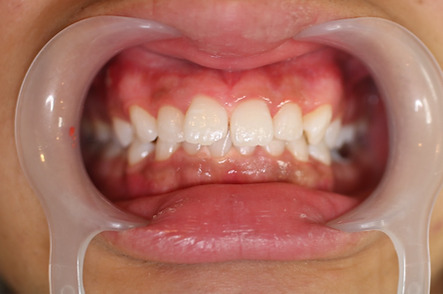

1矯正・マウスピース【治療例1】

治療前

治療後